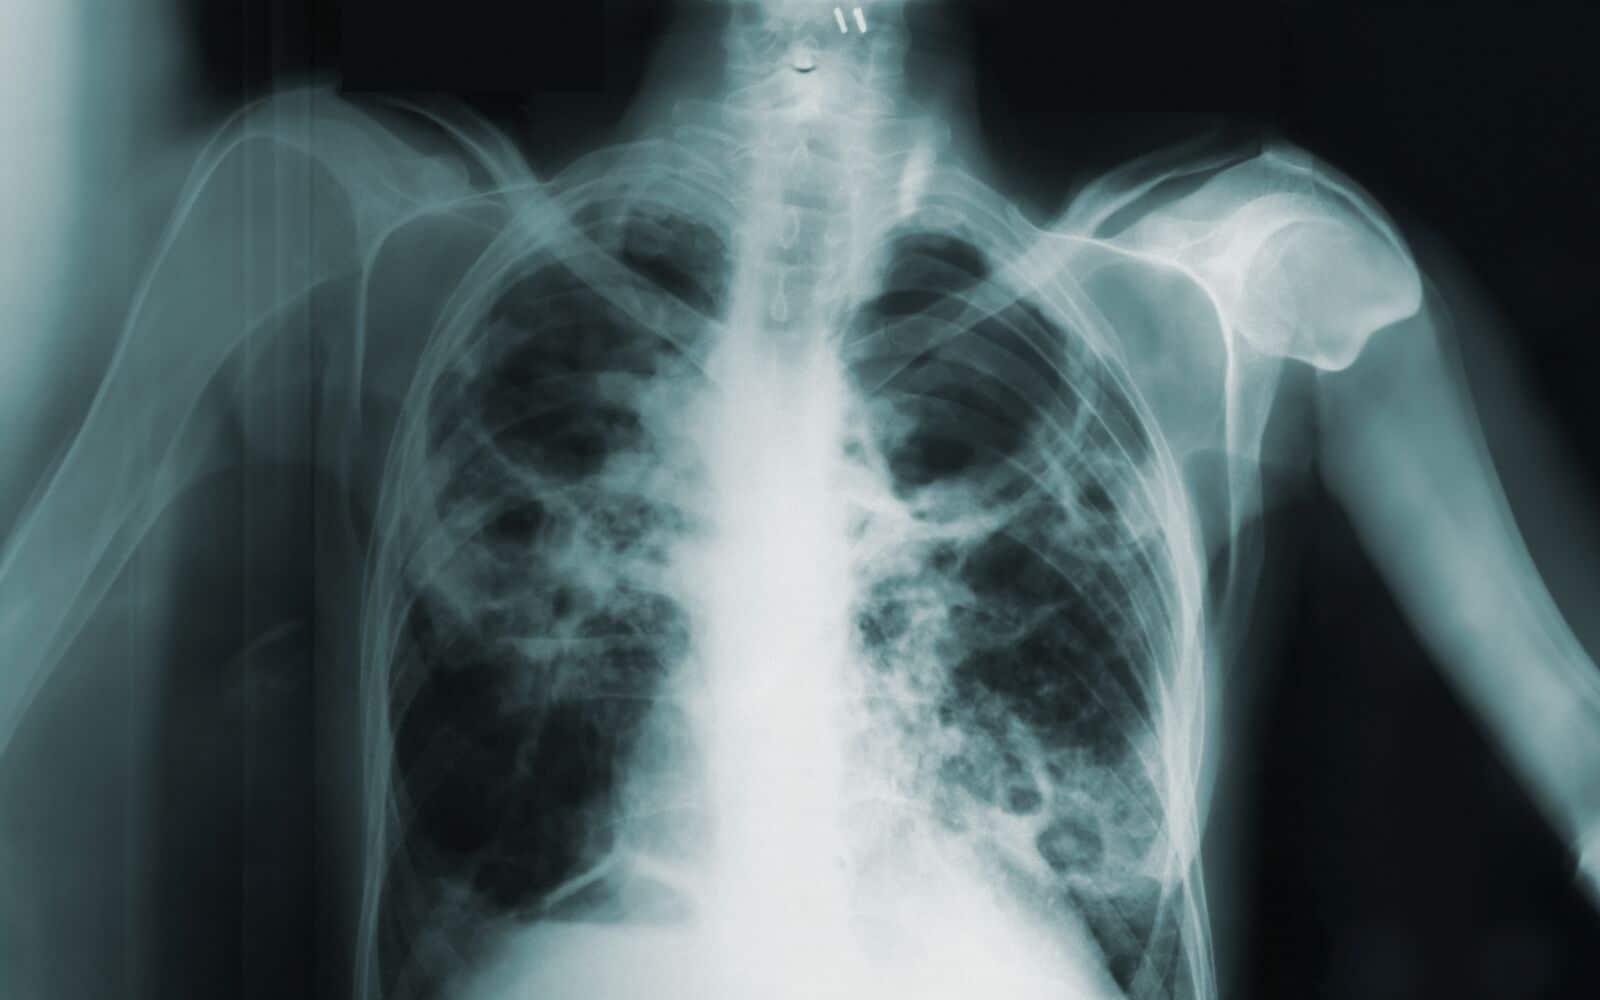

В Первоуральском политехническом техникуме подтвердили три случая туберкулеза среди учащихся.

Первые сообщения о болезни поступили от родителей в начале мая, но тогда администрация техникума не подтвердила наличие заболевания, пишет ИА Уральский меридиан. Сейчас в политехникуме проводятся меры по предотвращению распространения инфекции, включая дезинфекцию помещений и осмотр тех, кто мог контактировать с зараженными. Родителям рекомендуют следить за здоровьем своих детей и при появлении симптомов недомогания немедленно обращаться за медицинской помощью.

Фото: Frontiers